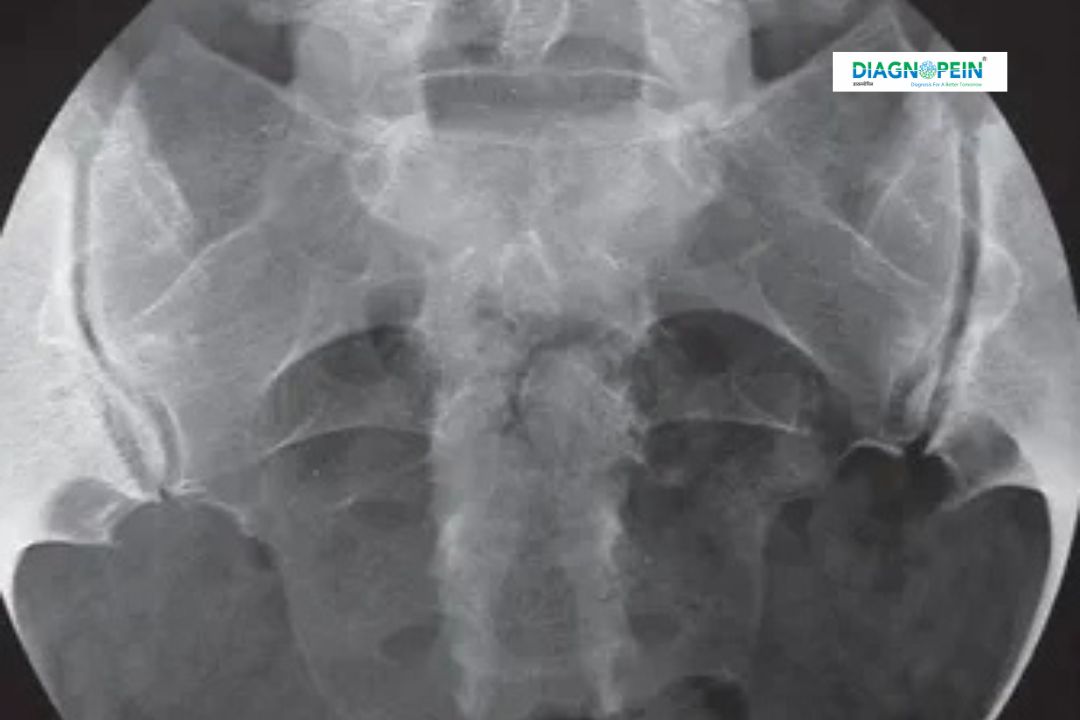

X-RAY SI JOINT (Sacroiliac Joint X-ray) is a diagnostic imaging test used to evaluate the sacroiliac joints, which connect the lower spine to the pelvis. These joints play a crucial role in supporting body weight and enabling smooth movement between the spine and hips. An X-RAY SI JOINT helps doctors detect structural abnormalities, inflammation, degeneration, fractures, or joint space changes that may be responsible for lower back pain, hip pain, or stiffness. This imaging test is commonly advised for patients experiencing chronic back discomfort, suspected arthritis, or trauma-related injuries.

The importance of X-RAY SI JOINT lies in its ability to identify conditions affecting the sacroiliac joints at an early stage. Disorders such as sacroiliitis, ankylosing spondylitis, osteoarthritis, and pelvic fractures often begin with subtle joint changes that can be detected through X-ray imaging. Early diagnosis allows timely medical intervention, reducing the risk of chronic pain and mobility issues.

One of the major benefits of X-RAY SI JOINT is its simplicity and speed. The test usually takes only a few minutes and does not require hospitalization. It delivers clear images of bone structures, helping doctors identify joint erosion, sclerosis, narrowing, or fusion.